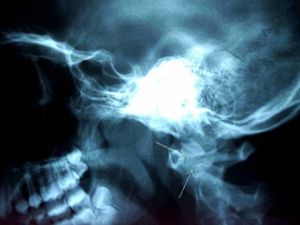

GPs should consider cancer of the larynx when patients report a persistent sore throat – particularly when combined with other seemingly low-level symptoms, research suggests.

A study of more than 800 patients diagnosed with cancer of the larynx found more than a 5% risk of cancer from a persistent sore throat combined with shortness of breath, problems swallowing or earache.

Currently, National Institute for Health and Care Excellence (Nice) guidelines recommend investigation for persistent hoarseness or an unexplained neck lump.

The new research from the University of Exeter gives greater insight into the combinations of symptoms GPs should be alert to when deciding who should be investigated for cancer.